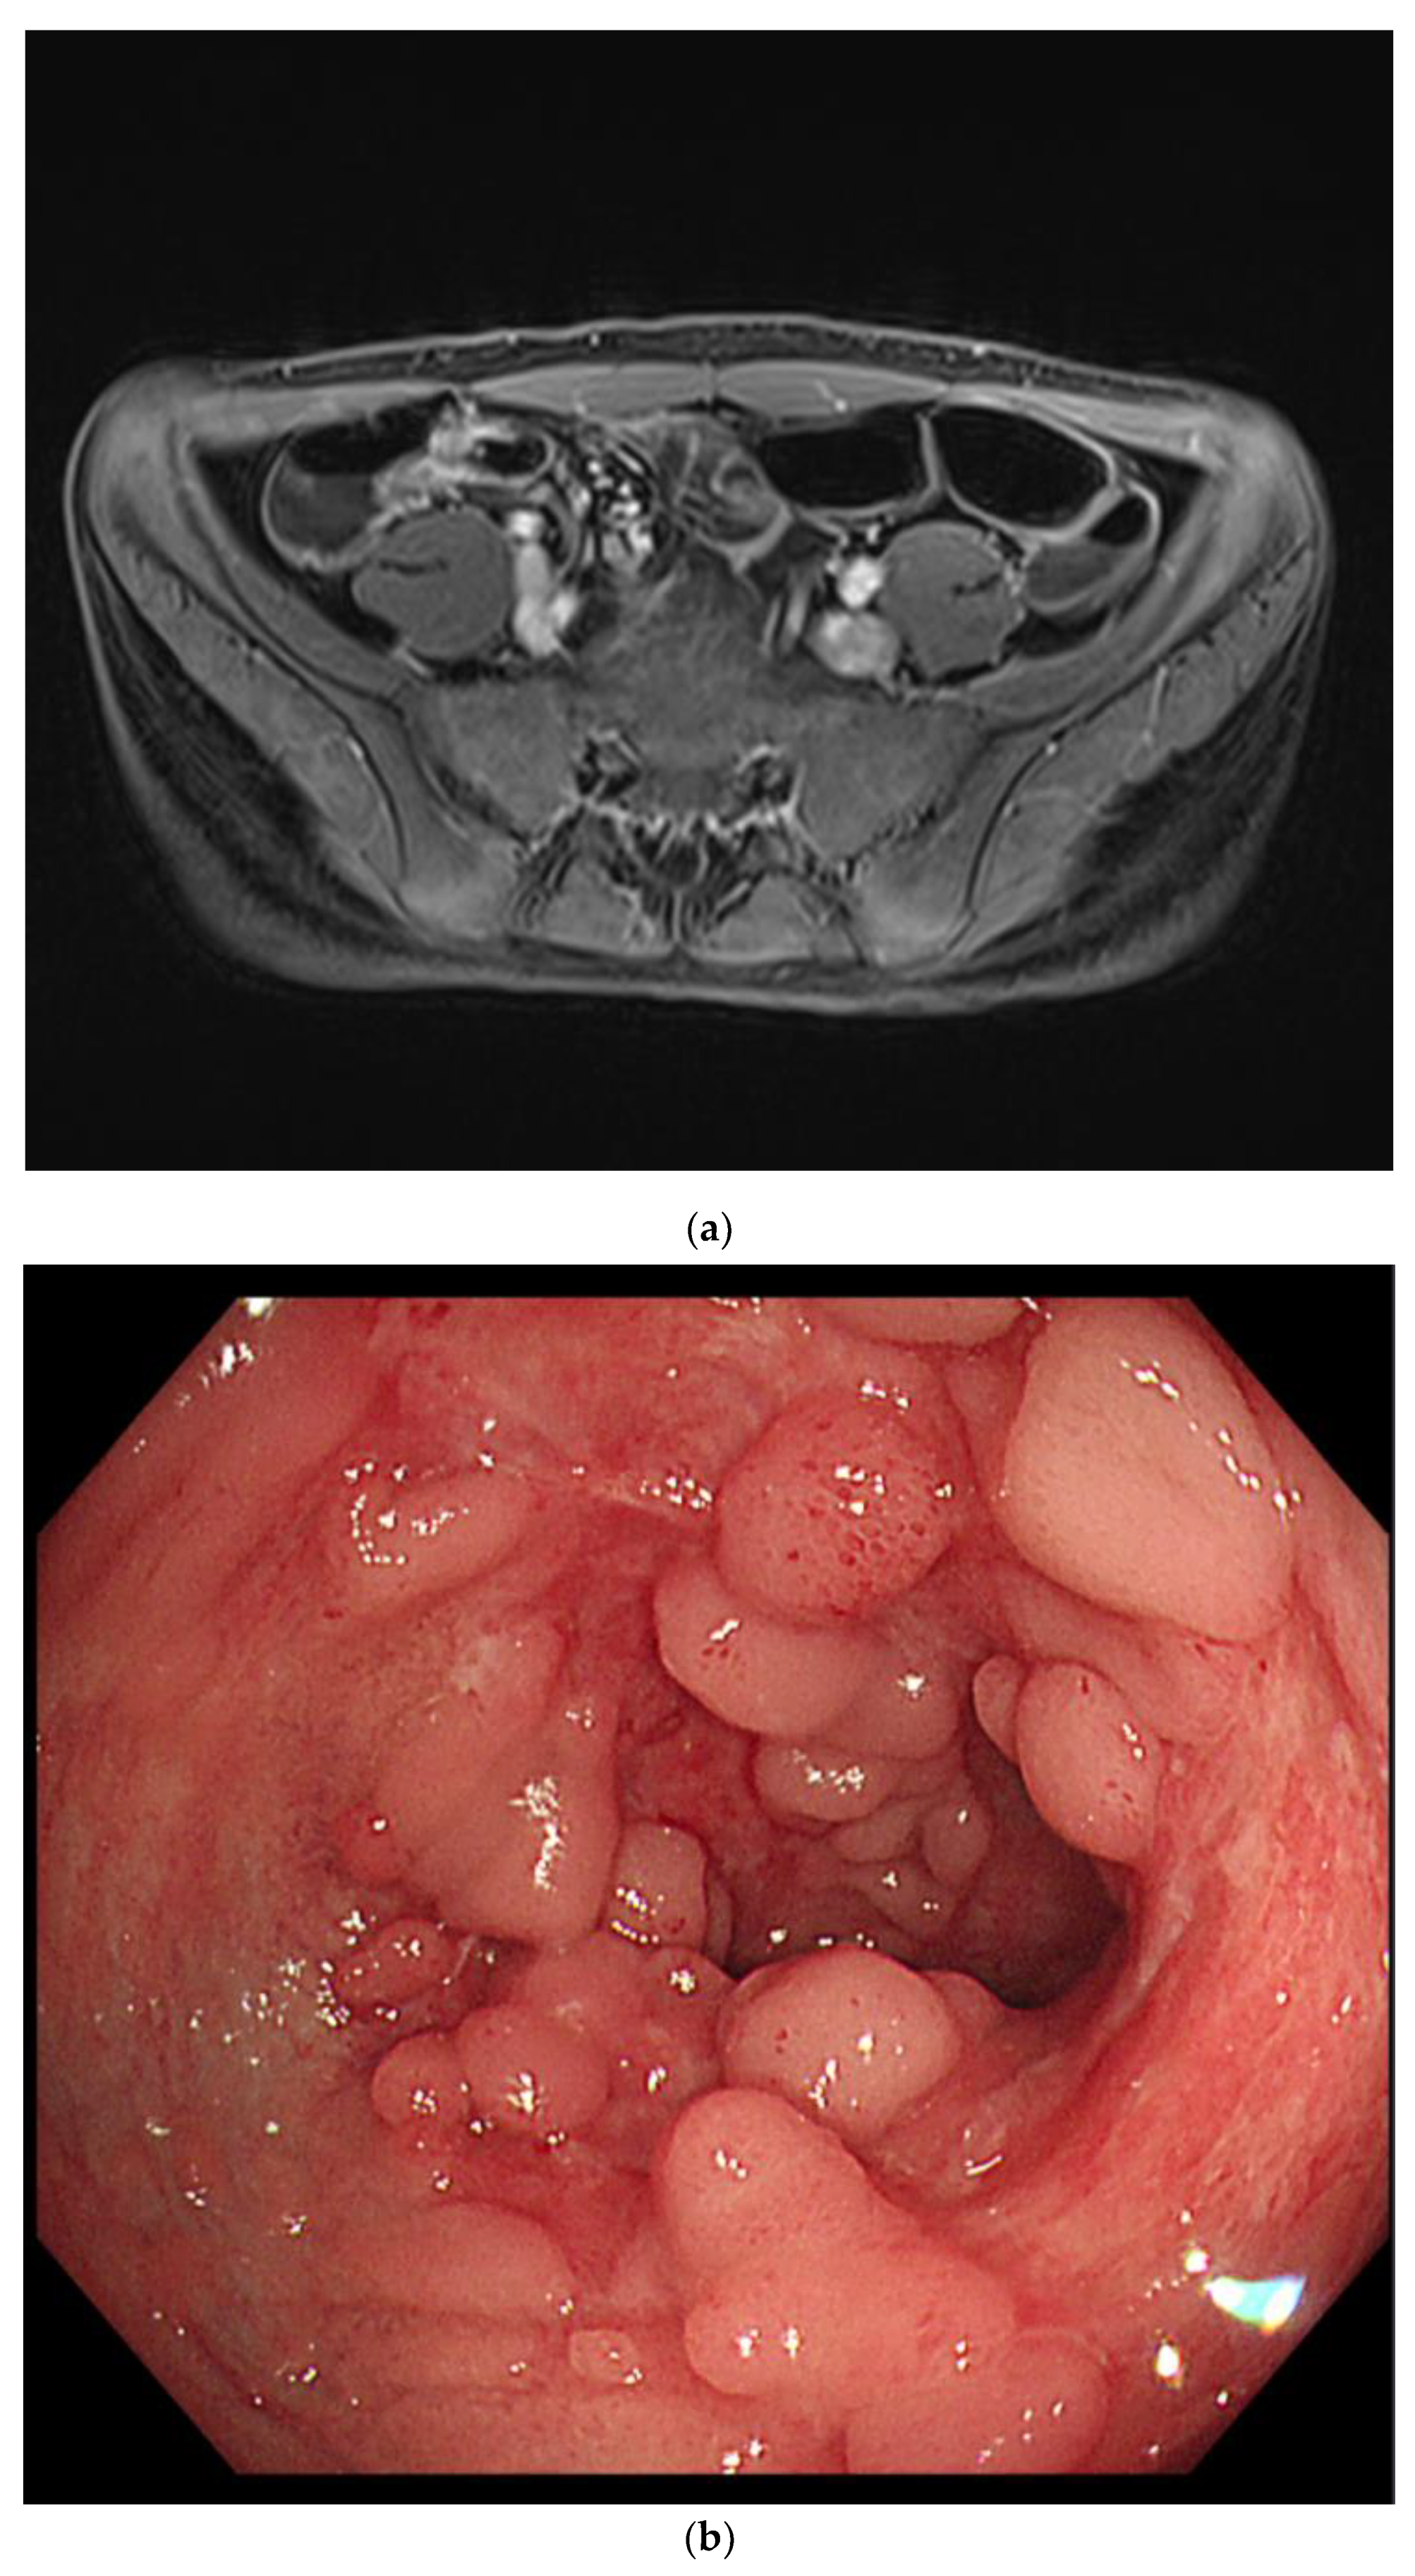

Intermittent episodes of bloody stools continued, and symptoms and vital signs were controlled through supportive care, including intravenous hydration and blood transfusion. CD was suspected, so he was treated with exclusive enteral nutrition with a steroid to control the myocarditis. On the 13th day of admission, the patient had no symptoms other than intermittent bloody stools. All cardiac markers were normal, and sST2 was also reduced to 98 ng/mL. Therefore, the patient was transferred to the general ward for diagnosis and treatment of IBD. MR enterography revealed terminal ileitis without stricture. Gastroduodenocolonoscopy revealed improvement in the ileocecal valve and terminal ileal ulceration with no other lesions (Figure 4).

Figure 4.

Magnetic resonance enterography demonstrated wall thickening of the distal ileum, including the ileocecal valve (a). Colonoscopy revealed healing scars and pseudopolyps of the terminal ileum (b).